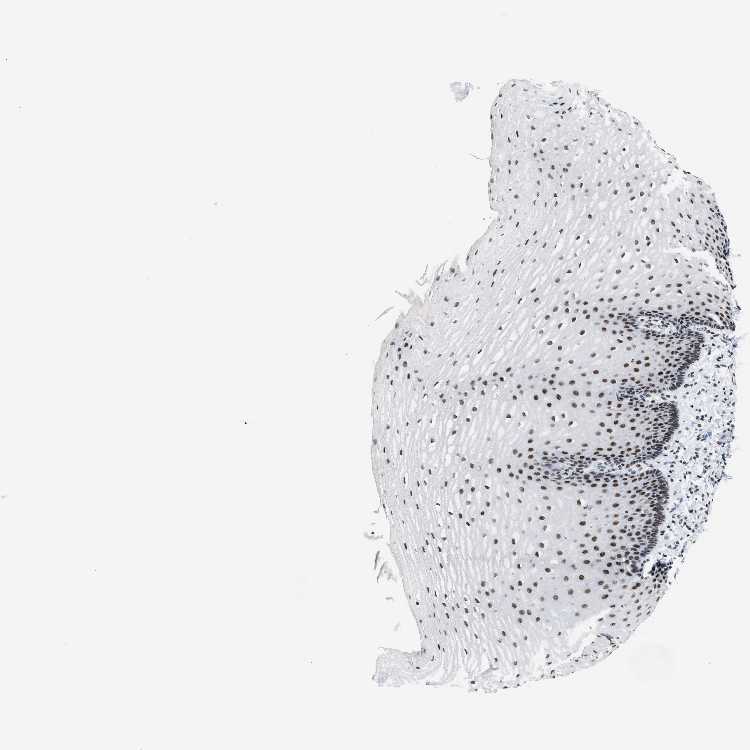

ESOPHAGUS - Antibody stainingi

Antibody staining in the annotated cell types in the current human tissue is reported as not detected, low, medium, or high, based on conventional immunohistochemistry profiling in selected tissues. This score is based on the combination of the staining intensity and fraction of stained cells.

Each image is clickable and will lead to virtual microscopy that enables deeper exploration of all samples and also displays staining intensity scores, fraction scores and subcellular localization as well as patient and tissue information for each sample.

Antibody HPA019907Antibody HPA019943Antibody CAB072827

Squamous epithelial cells HighHighHigh